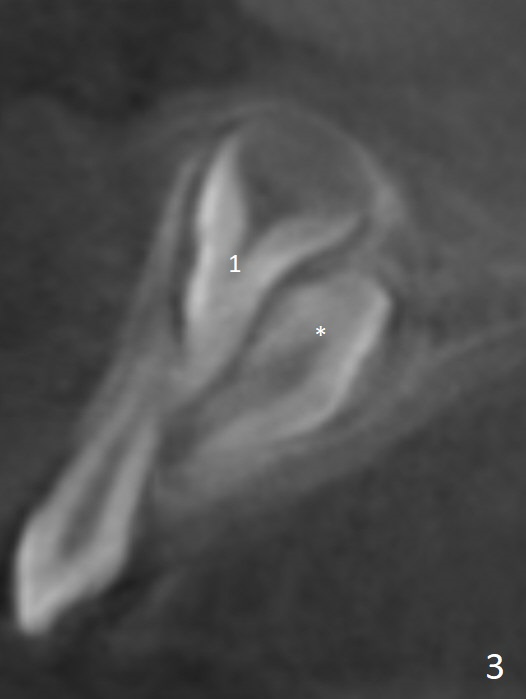

CBCT taken on 11/03/2017 confirms the findings mentioned above (Fig.2-4).  These 2 supernumerary teeth are close palatally (Fig.3 (for UR1), 4 (UL1)).